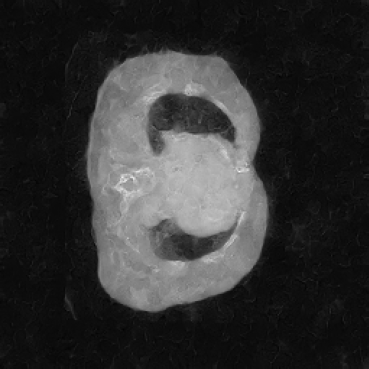

The hypothesis of this experiment is that if the synthetic images generated by our model resemble real medical images in distribution, a segmentation network trained on real data should yield similar performance on synthetic data. By comparing the segmentation results across real and synthetic images, we can quantitatively assess the structural fidelity and semantic consistency of the generated data. The results confirm that segmentation performance on synthetic images is highly comparable to that on real images, indicating that our model successfully captures anatomically relevant structures. This suggests that synthetic data are not only realistic but also potentially beneficial as an augmentation strategy to improve segmentation tasks. Visualizations of the segmentation output are presented in Figure 6.

In our approach, we employ a compression factor of 4 to encode 3D medical images into the latent space. This level of compression reduces the spatial resolution of the original image (e.g., from 256×256 to 64×64 per slice), while still preserving the essential anatomical structures and semantic content. The latent representation at this scale offers a favorable trade-off between dimensionality reduction and semantic fidelity. Specifically, although fine-grained textures are simplified, key structural patterns (e.g., organ boundaries, lesion shapes) remain visually distinguishable and semantically coherent. As the compression rate increases, the latent representations become progressively more abstract. With lower compression (e.g., 2× or 4×), the latent features preserve key anatomical structures and spatial layouts, making them beneficial for our semantic image synthesis task in latent space, as the model can operate on compressed representations that retain sufficient semantic information without being overwhelmed by high-frequency noise. In contrast, higher compression rates (e.g., 8× or above) lead to a loss of fine-grained details and reduced semantic fidelity. The choice of a 4× compression thus ensures that the latent features are compact and meaningful, facilitating effective conditional generation while significantly reducing computational overhead. We therefore adopt a 4× compression as a compromise between computational efficiency and semantic preservation. The corresponding 2D slices in image space and latent space are shown in Figure 7.